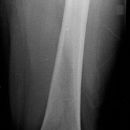

Proximaler Oberschenkel lateral (2. Ebene)

Fraktur, Z.n. Osteosynthesematerial

Seitenlage

aufzunehmende Bein liegt mit Außenseite auf

in der Hüfte möglichst gestreckt, Knie angewinkelt

gesunde Bein aufgestellt oder gestreckt je nach Beweglichkeit

ZS senkrecht auf Objekt- und Detektormitte

Länge voll ab Spina iliaca anterior superior, lateral Hautgrenze

Oberschenkel wird exakt lateral abgebildet, Hüftgelenk gut einsehbar, Schenkelhals stark verkürzt und durch den Trochanter major verdeckt.